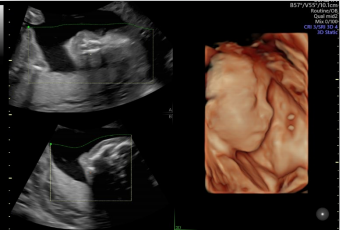

作為超聲領(lǐng)域的領(lǐng)導(dǎo)者,GE醫(yī)療一直走在全球前列。從世界第一臺(tái)A型超聲、第一臺(tái)實(shí)時(shí)B型超聲、第一把腔內(nèi)探頭、第一臺(tái)3D/4D超聲……一代代的經(jīng)典由此誕生,Voluson超聲也成為了婦產(chǎn)領(lǐng)域的代名詞。

截至目前,Voluson系列彩超已經(jīng)覆蓋全球80%以上具有婦產(chǎn)生育服務(wù)的醫(yī)院,每年服務(wù)全球孕產(chǎn)婦高達(dá)2.3億次。此外,全球近85%以上的婦產(chǎn)超聲文獻(xiàn)都是基于Voluson系列撰寫(xiě)而來(lái)。